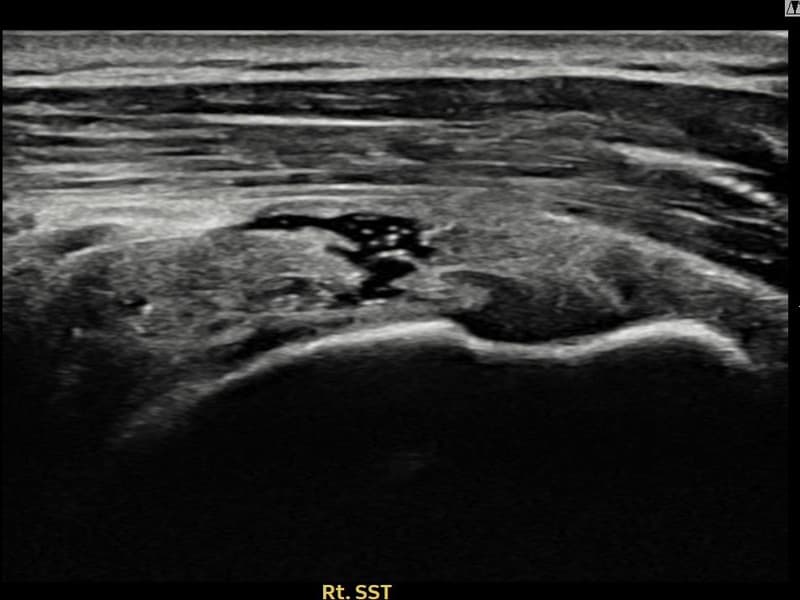

术前

术前超声确认右侧 冈上肌腱 部分撕裂 + 건내 석회화,右侧冈上肌腱回声不连续伴肌腱缺损(9mm × 4mm (肌腱厚度约38%缺损))。术后超声显示撕裂部位充满再生组织,肌腱连续性恢复,回声模式正常化。